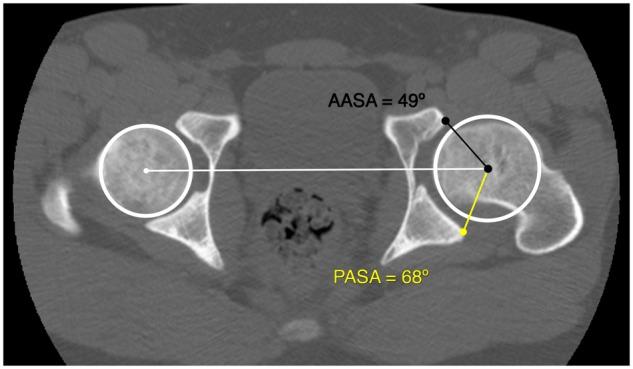

To evaluate the acetabular morphology in healed Legg-Calvé-Perthes disease after skeletal maturity using computed tomography (CT) scan and to compare with matched controls. We identified 33 (37 hips) patients with healed Legg-Calvé-Perthes disease and closed triradiate cartilage who underwent pelvic CT scan. Each patient was matched based on sex, age and side to a subject with no history of hip disease who had undergone pelvic CT evaluation because of abdominal pain. Both cohorts had 23 (70%) males and mean age of 16.4-16.5 ± 3.6 years. Two independent readers assessed lateral center-edge angle (LCEA), acetabular inclination angle (IA), acetabular depth-width ratio (ADR), acetabular version 10 mm below the dome (cranial) and at the acetabular center and anterior (AASA) and posterior acetabular sector angles (PASA). All measurements had good to excellent interobserver agreement (intraclass coefficients ≥ 0.87). The hips in the Legg-Calvé-Perthes disease cohort had a smaller mean ± standard deviation (SD) superior, anterior and posterior acetabular coverage as assessed by LCEA (13.2° ± 10.7° versus 28.2° ± 3.4°;  < 0.0001), IA (11.6° ± 6.7° versus 3.5° ± 2.8°;  < 0.0001), AASA (52.4° ± 9.5° versus 59.3° ± 5.0°;  = 0.001) and PASA (79.3° ± 5.9° versus 92.3° ± 5.5°;  < 0.0001) compared with controls. The acetabulum was shallower (ADR 287 ± 45 versus 323 ± 28;  = 0.0002) and the acetabular version was decreased cranially (0.4°±9.2° versus 8.2°±6.8°;  = 0.0002) and at the acetabular center (13.7°±5.1° versus 17.2° ±3.8°;  = 0.004) in Legg-Calvé-Perthes disease hips. After skeletal maturity, hips with healed Legg-Calvé-Perthes disease have shallower and more cranially retroverted acetabula, with globally reduced coverage of the femoral head compared with age-, sex- and side-matched control hips.

目的是使用计算机断层扫描(CT)评估骨骼成熟后愈合的Legg-Calvé-Perthes病的髋臼形态,并与匹配的对照组进行比较。我们确定了33例(37髋)患有愈合的Legg-Calvé-Perthes病且三放射软骨闭合的患者,他们接受了骨盆CT扫描。根据性别、年龄和患侧,为每位患者匹配一名因腹痛接受骨盆CT评估且无髋关节疾病史的受试者。两组均有23例(70%)男性,平均年龄为16.4 - 16.5±3.6岁。两名独立的阅片者评估了外侧中心边缘角(LCEA)、髋臼倾斜角(IA)、髋臼深度宽度比(ADR)、髋臼穹顶下方10毫米(颅侧)、髋臼中心以及前方(AASA)和后方髋臼扇形角(PASA)。所有测量的观察者间一致性良好至优秀(组内相关系数≥0.87)。与对照组相比,Legg-Calvé-Perthes病队列中的髋关节,通过LCEA评估的髋臼上、前和后覆盖范围的平均±标准差(SD)较小(13.2°±10.7°对28.2°±3.4°;<0.0001),IA(11.6°±6.7°对3.5°±2.8°;<0.0001),AASA(52.4°±9.5°对59.3°±5.0°;=0.001)和PASA(79.3°±5.9°对92.3°±5.5°;<0.0001)。Legg-Calvé-Perthes病髋关节的髋臼较浅(ADR 287±45对323±28;=0.0002),髋臼旋转在颅侧(0.4°±9.2°对8.2°±6.8°;=0.0002)和髋臼中心(13.7°±5.1°对17.2°±3.8°;=0.004)降低。骨骼成熟后,与年龄、性别和患侧匹配的对照髋关节相比,愈合的Legg-Calvé-Perthes病髋关节的髋臼更浅且颅侧后倾更明显,股骨头的整体覆盖范围减小。